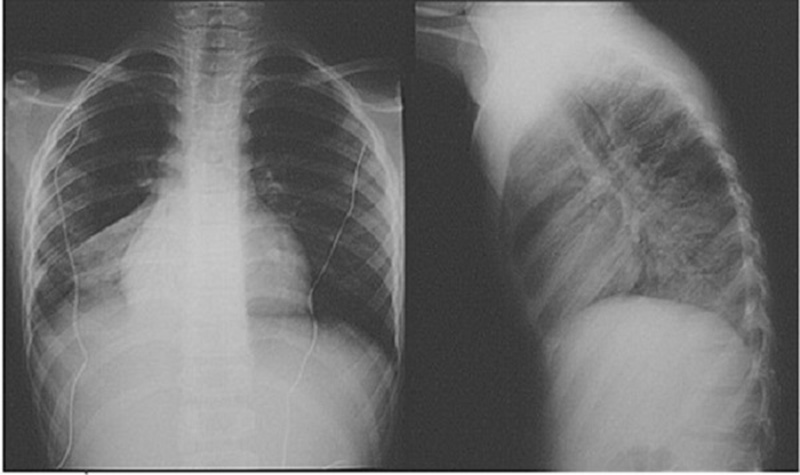

Bác sỹ chụp phim, rồi kêu với tôi: “Chết, chết, em phát hiện trong ngực của chị, mỗi bên có một khối u lớn, kích thước 150x110mm, mà lại nổi hạch xung quanh. Em nghi ngờ khối u này là ác tính, bởi khối u lành tính hiếm khi có hạch như vậy”. Tôi nghe bác sỹ nói vậy mà bủn rủn chân tay, trời đất như sụp xuống.

Tôi đi bệnh viện để kiểm tra thì bác sỹ nói không còn hạch trong ngực, khối u cũng chỉ còn rất nhỏ là 4mm, phải dò kỹ lắm mới thấy. Quan trọng là sức khoẻ của tôi trở lại trạng thái tốt như trước khi phát hiện ra khối u, tinh thần sảng khoái, vui tươi.